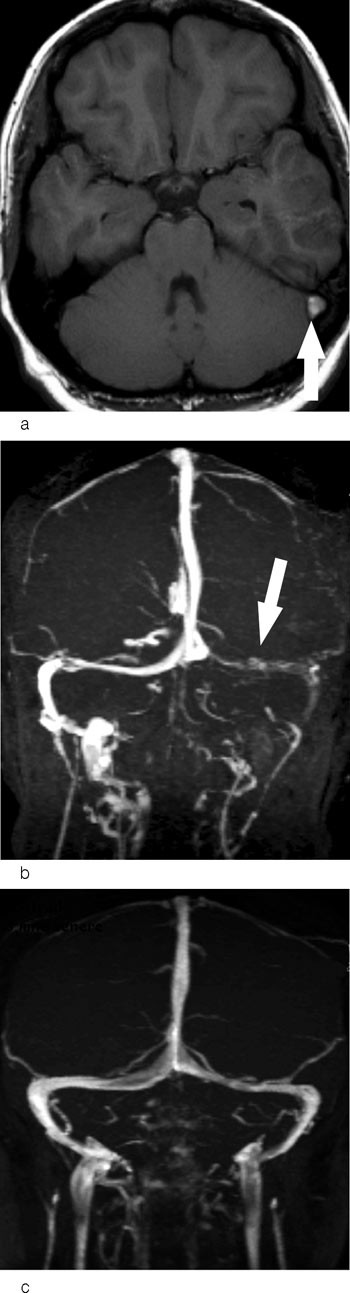

Et typisk bildediagnostisk tegn ved cerebral venetrombose er en fyllingsdefekt i venesinus (fig 1). Disse fyllingsdefektene er hypertette på CT. I sinus sagittalis superior vil fyllingsdefekten ofte ha en trekantet form. På MR vil signalet i tromben variere med alderen (fig 2). Trombene kan også strekke seg retrograd fra venesinus og inn i de kortikale venene. Sekundære forandringer til sinusvenetrombose er hjerneødem og venøse infarkter, typisk beliggende subkortikalt og kortikalt (fig 3). I motsetning til arterielle infarkter vil de venøse ikke følge forsyningsområdene for de store cerebrale arteriene, en annen forskjell er større ødem ved venøse infarkter (18). Venøse infarkter vil ofte være hemoragiske, og på såkalte hemosekvensbilder vil man se blodproduktene som områder med lavt signal.

Ved bildediagnostikk av cerebral venetrombose er det viktig å være oppmerksom på noen fallgruber. Det er en betydelig grad av anatomiske variasjoner i de durale venesinuser, dette gjelder særlig i sinus transversus. Hos vel to tredeler av alle mennesker er høyre sinus transversus større enn venstre. Sinus transversus er hypoplastisk eller manglende på den ene siden hos nær en tredel, vanligvis på venstre side. En manglende fremstilling av sinus transversus må derfor ikke uten videre tolkes som en okklusjon fremkalt av trombe (fig 4). Pacchioni-granulasjoner i venesinuser er en normalvariant (19). Disse granulasjonene kan bli opptil et par centimeter og delvis okkludere venesinus (fig 4). De kan skilles fra tromber ved at de har en typisk lokalisasjon ved innmunningen av Labbes vene i sinus transversus og ved at signalmønsteret er annerledes.